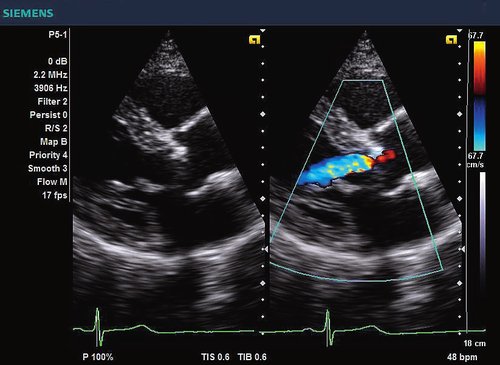

Siemens ACUSON X300 PE Beschreibung

Das Siemens Acuson X300 PE ist ein mittelklassiges Herz-Kreislauf-Ultraschallgerät mit gemeinsamen Servicefunktionen. Die Premiumedition verfügt über 4D-Technologie und eine doppelte Auswahl an Sonden; zusammen mit vielen hochwertigen Funktionen ist sie in einem mittleren Preissegment erhältlich. Das Siemens ACUSON X300 PE bietet eine Vielzahl von Lösungen, einschließlich allgemeine Bildgebung, interdisziplinäre  Dienstleistungen, OB/GYN, Kardiologie, Urologie, Endokrinologie, Notfallmedizin und viele andere fachspezifische Anwendungen.

• Features: 3D, 4D, Farb/Doppler